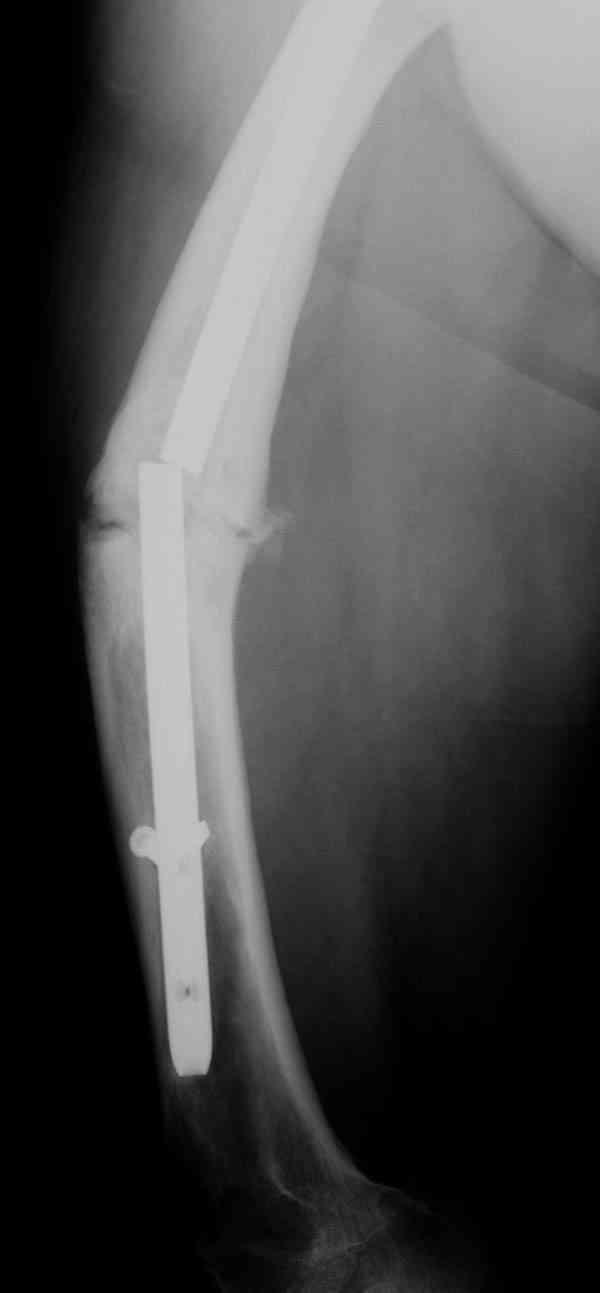

Уважаемые коллеги! У пациента 50-ти лет ложный сустав голени, перелом интрамедуллярного штифта. Перелому около 2 лет, ходить с полной нагрузкой начал через 3 мес. после операции. Боли при ходьбе почувствовал около 2 мес. назад. На данный момент ходит с полной нагрузкой без посторонней опоры. Среди коллег развернулась дискуссия по поводу способа оперативного лечения: -удаление штифта с перештифтовыванием блокированным штифтом с рассверливанием и остеотомией м\б кости -стабилизация зоны ложного сустава по медиальной поверхности LCP-пластиной с декортикацией или без -удаление штифта или без и синтез в АВФ с декотрикацией или без и остеотомией м\б кости

Наиболее быстро достичь опорности без боли и внешних приспособлений - удаление и блокируемый реостеосинтез с рассверливанием. Лучше бы тоже с

восстановлением оси (отклоняющая спица в дистальном отломке, чтобы новый стержень прошел не в старый канал, а кзади от него), еще и для создания дополнительного напряжения тканей в области несращения. Открывать зону несращения не надо.

Сросшаяся малоберцовая как распорка привела к образованию ложного сустава. В таких случаях удаляем сломанный штифт и проводим стимуляцию ложного сустава рассверливанием. Рассверливание канала создает стимуляцию на месте ложного сустава, и динамический вариант блокировки штифта с большим диаметром создаст стабильность. Ранняя нагрузка после остеотомии малоберцовой приведет к сращению ложного сустава.